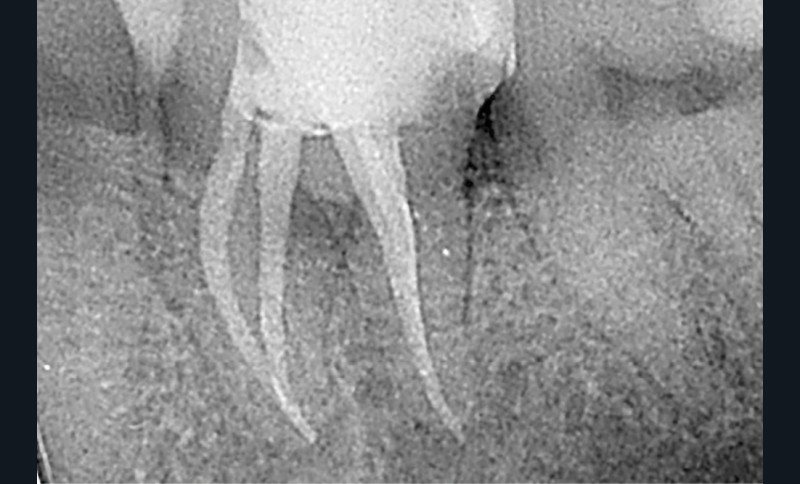

Les 2 objectifs principaux de l’obturation sont de prévenir une nouvelle entrée bactérienne et d’emmurer les bactéries résiduelles [4]. Nous avons réalisé une technique d’obturation à chaud en trois vagues, avec de la gutta percha et du ciment oxyde de zinc-eugenol. La question d’une obturation technique monocône-biocéramique s’est posée afin de ne pas exercer de contraintes mécaniques supplémentaires par application de technique de compactage de gutta-percha sur cette racine fragile. Bien que certaines études ne montrent aucune différence significative sur la technique d’obturation et la création de fissure [5], l’utilisation d’une technique d’obturation intuitivement la moins traumatique possible aurait pu s’avérer plus pertinente dans cette situation clinique [6] (fig. 7 et 8).

Lors du suivi clinique et radiologique à 24 mois, nous observons une cicatrisation de la LIPOE, et la dent est asymptomatique (fig. 11 et 12).